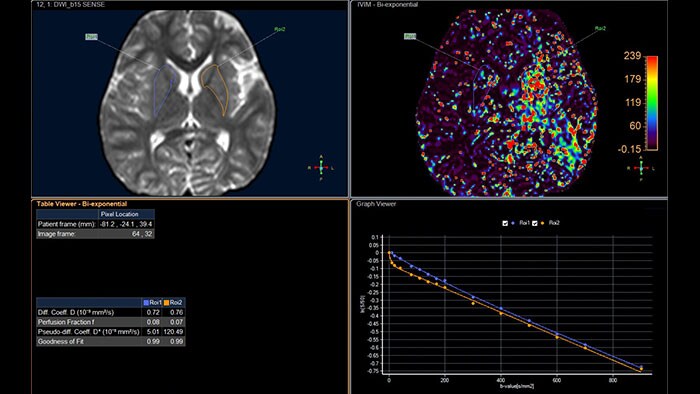

Computed diffusion weighted images at a b-value of choice

The application is intended to view, process and analyze MRI Diffusion Weighted Images. It calculates and displays cDWI at a

b-value of choice (from 0 to 5,000 s/mm2) and provides advanced supportive analysis and visualization tools of diffusion MRI images and parametric maps.

Analyze diffusion and anisotropic properties of tissue

Designed to analyze diffusion and anisotropic properties of tissue. The application evaluates DWI series to generate parametric maps such as ADC and eADC. For Diffusion Tensor Imaging data, additional parametric maps are generated, including fractional anisotropy, axial diffusivity or radial diffusivity.

Benefits